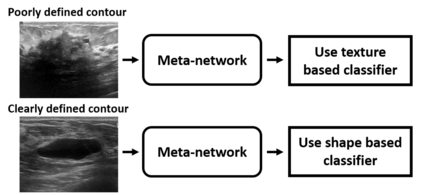

Standard classification methods based on handcrafted morphological and texture features have achieved good performance in breast mass differentiation in ultrasound (US). In comparison to deep neural networks, commonly perceived as "black-box" models, classical techniques are based on features that have well-understood medical and physical interpretation. However, classifiers based on morphological features commonly underperform in the presence of the shadowing artifact and ill-defined mass borders, while texture based classifiers may fail when the US image is too noisy. Therefore, in practice it would be beneficial to select the classification method based on the appearance of the particular US image. In this work, we develop a deep meta-network that can automatically process input breast mass US images and recommend whether to apply the shape or texture based classifier for the breast mass differentiation. Our preliminary results demonstrate that meta-learning techniques can be used to improve the performance of the standard classifiers based on handcrafted features. With the proposed meta-learning based approach, we achieved the area under the receiver operating characteristic curve of 0.95 and accuracy of 0.91.